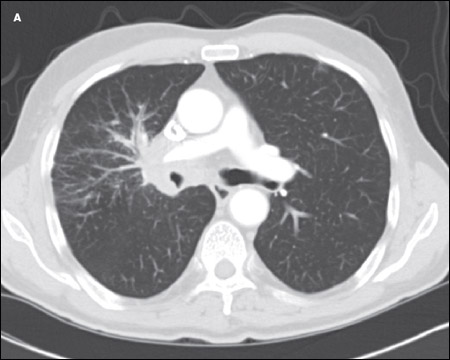

A CT scan of the chest showed an amorphous soft tissue mass that encased and constricted the right main pulmonary artery and the right main stem bronchus (A). Extensive round masses were visible in the liver; the largest mass was in the right medial hepatic lobe and measured 2.7 × 2.4 cm (B).

The central location of the lung mass, its rapid growth, and the patient's strong smoking history all pointed to small-cell lung cancer, B. Also, there is a noted propensity for bone marrow involvement in small-cell lung cancer, which might have explained the patient's neutropenia and thrombocytopenia.

SCLC typically presents as a large central mass (as in this patient) with mediastinal adenopathy. SCLC can infiltrate the submucosa, causing either intrinsic or extrinsic compression of the bronchi. SCLC has a propensity for spreading to the liver, brain, bone, and bone marrow. The neutropenia and thrombocytopenia seen in this man can be explained by the infiltration of his bone marrow by the SCLC. In a series of 129 patients with SCLC, 30% had bone marrow involvement. However, in only 2.3% was the bone marrow the only site of metastatic disease.7 Other presenting symptoms include cough, dyspnea, hemoptysis, chest pain, postobstructive pneumonia, and the paraneoplastic syndromes mentioned above.